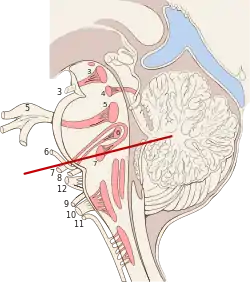

The three distinct parts of the brainstem are colored in this sagittal section of a human brain. | |

The brainstem (or brain stem) is the stalk-like[1]: 152 part of the brain that interconnects the cerebrum and diencephalon with the spinal cord.[2] In the human brain, the brainstem is composed of the midbrain, the pons, and the medulla oblongata.[3][1]: 152 The midbrain is continuous with the thalamus of the diencephalon through the tentorial notch.[1]: 152

The parts of the brainstem are the midbrain, the pons, and the medulla oblongata; the diencephalon is sometimes considered part of the brainstem.[7]: 248